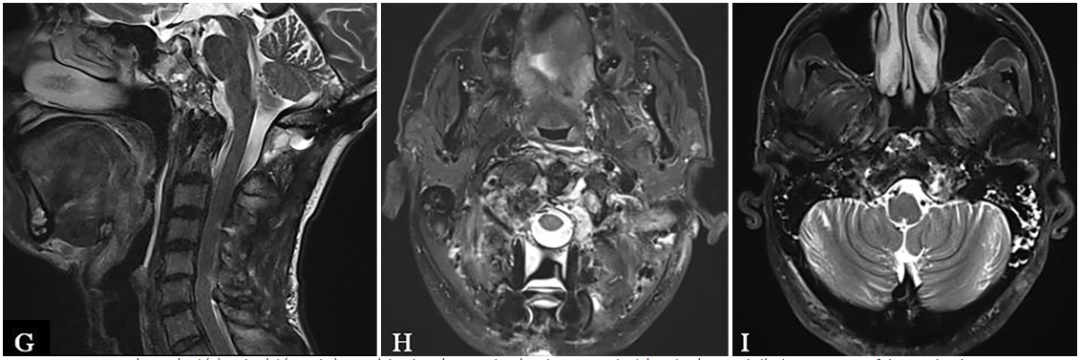

▼术后MRI显示NTR(图4G-I)。

图片G-I:术后MR显示椎前、下斜坡和椎后的肿瘤被切除。